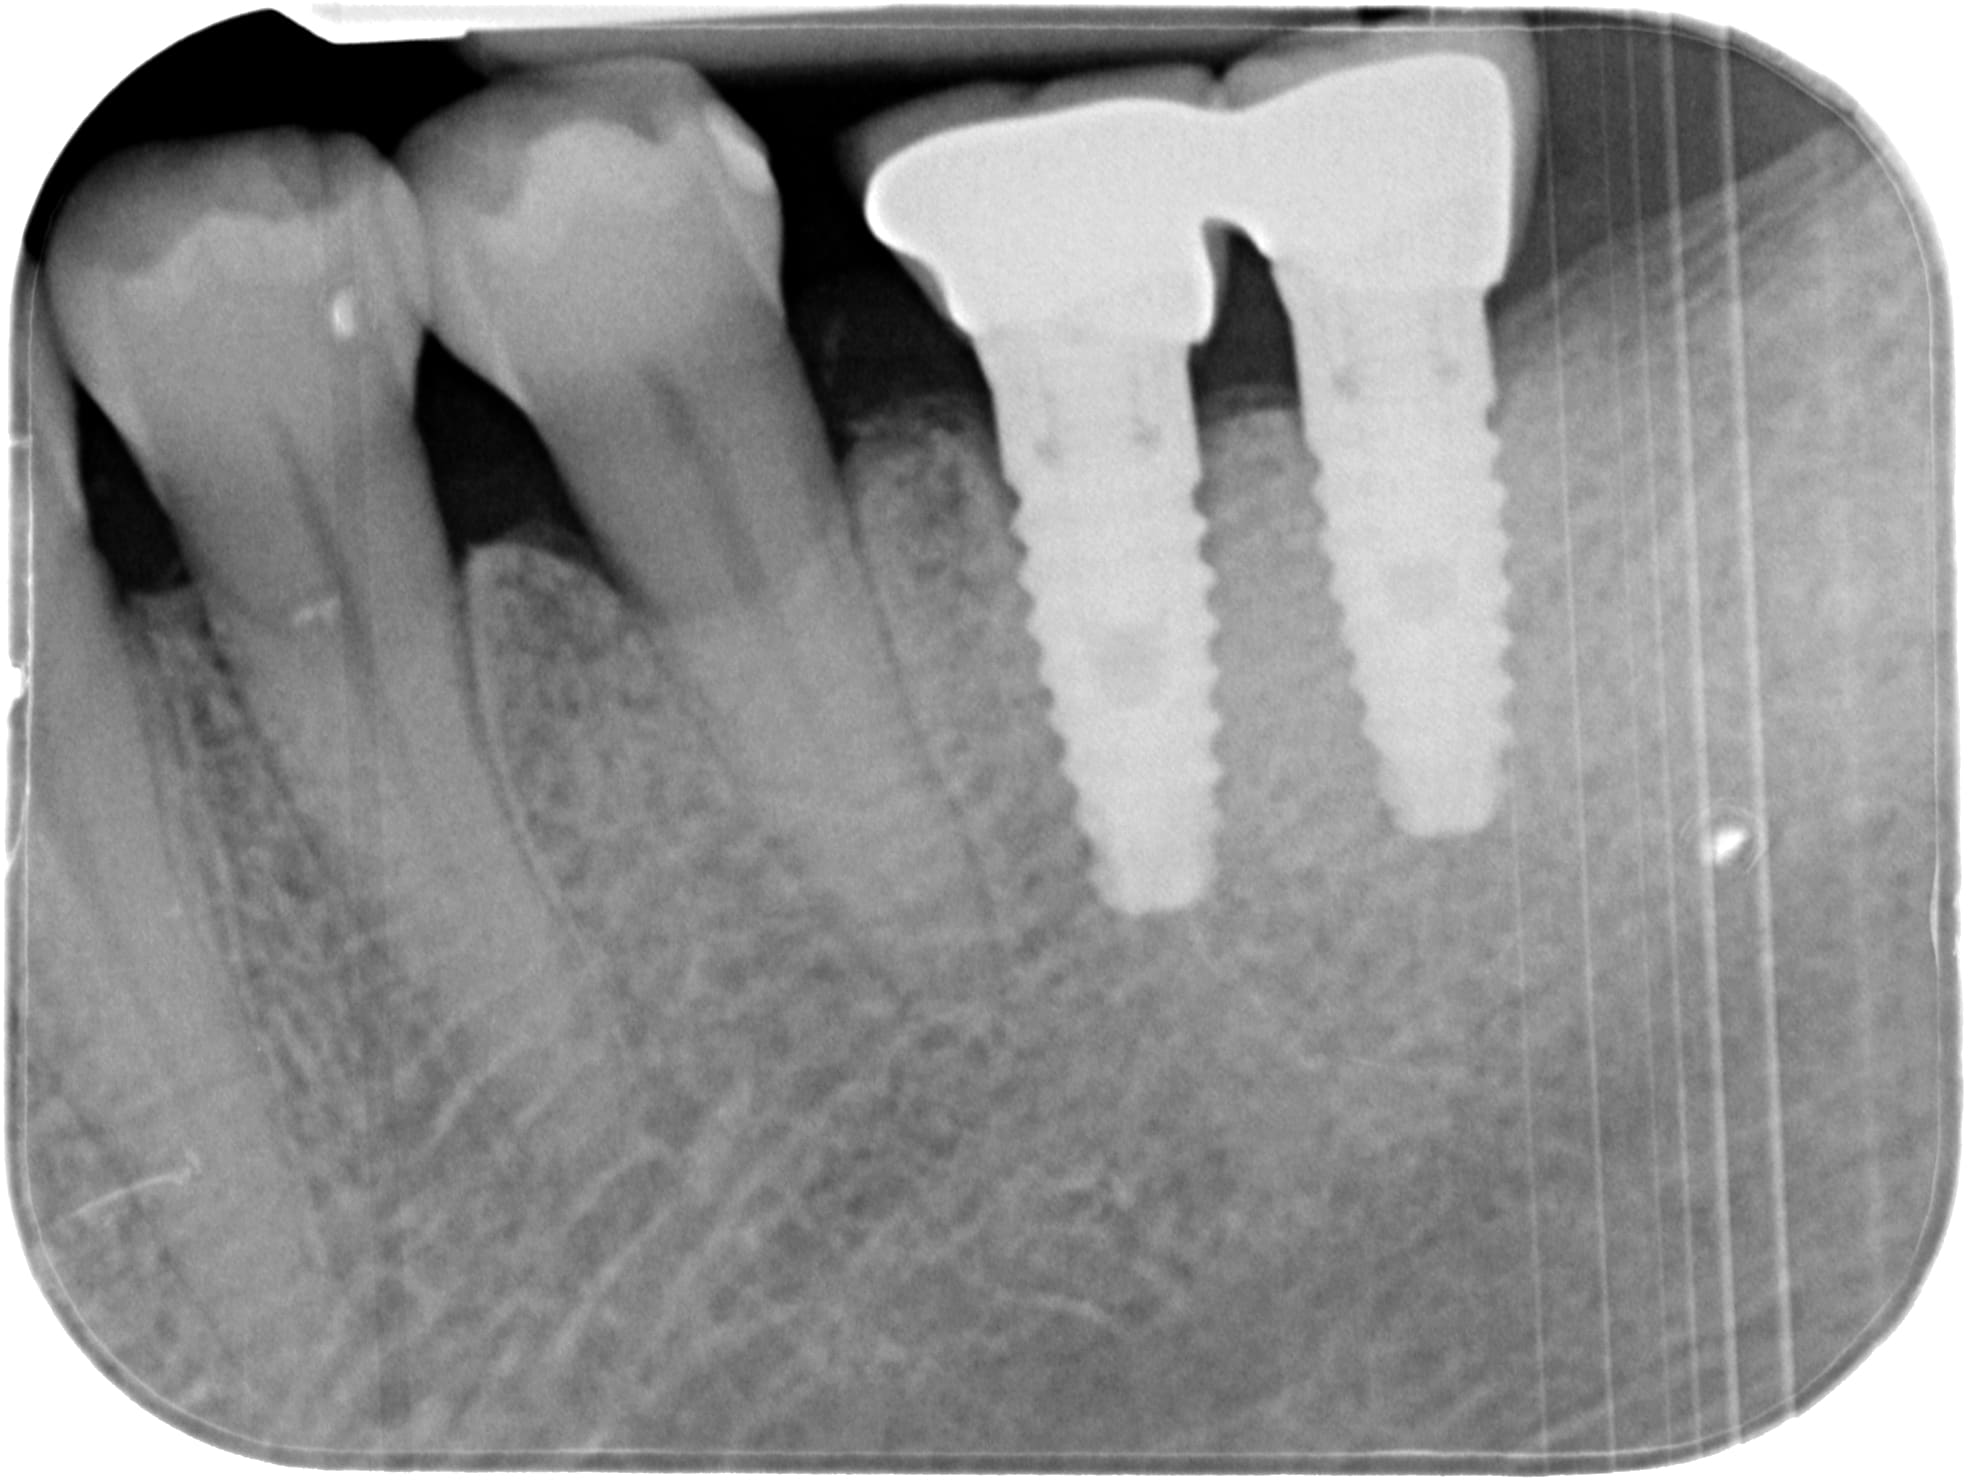

Bonjour à tous, avez vous une idée de la marque de ces implants posées il y a environ 15 ans ?

dommage que la radio soit pas un peu plus nette/contrastée....

mais ils ont une bonne gueule de biohorizons....